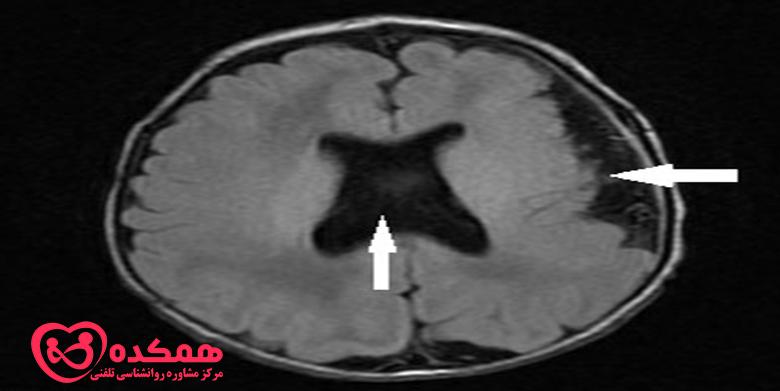

این نوع شدیدتر دیسپلازی قشر مغز است که در آن سلولهای مغزی علاوه بر آرایش غیرطبیعی سلولها، غیرعادی به نظر میرسند. این نوع بیشتر در کودکان دیده می شود و هر دو قسمت گیجگاهی و پیشانی مغز را درگیر می کند. معمولاً در تصویربرداری رزونانس مغناطیسی (MRI) دیده می شود.

پزشک شما تشخیص صرع را بر اساس سلامت فرزندتان، سابقه پزشکی گذشته و سابقه خانواده شما انجام می دهد. آن ها همچنین یک معاینه فیزیکی دقیق انجام می دهند. و سعی می کنند تا آن جا که می توانند از شما در مورد تشنج های فرزندتان یاد بگیرند. آن ها همچنین ممکن است آزمایش خون انجام دهند. اگر پزشک مشکوک به دیسپلازی قشر مغز باشد، آزمایشات بیشتری تجویز خواهد شد. این ها شامل الکتروانسفالوگرام (EEG) و تصویربرداری رزونانس مغناطیسی (MRI) است.

اگر MRI نرمال باشد، پزشک آزمایشهای تصویربرداری دیگری مانند اسکن توموگرافی گسیل پوزیترون (PET)، SISCOM یا مگنتوآنسفالوگرافی (MEG) را برای تعیین محل وقوع تشنج تجویز میکند. دیسپلازی کانونی کورتیکال به ندرت در سی تی اسکن قابل مشاهده است و گاهی در MRI نیز غیرقابل تشخیص باقی می ماند. در موارد دیگر، ناحیه آسیب دیده که در اسکن MRI نشان داده میشود. در واقع میتواند بزرگتر از چیزی باشد که توسط MRI نشان داده میشود. این می تواند بر نتایج جراحی تاثیر بگذارد.

تست های مختلف تصویر برداری برای دیسپلازی قشر مغز

به همین دلیل، پزشکان از سایر تستهای تصویربرداری قدرتمند مانند ترکیب MRI با وضوح بالا و تست FDG-PET برای شناسایی دیسپلازی قشر مغز استفاده میکنند. تمرکز اصلی درمان دیسپلازی قشر مغز، کنترل تشنج است.